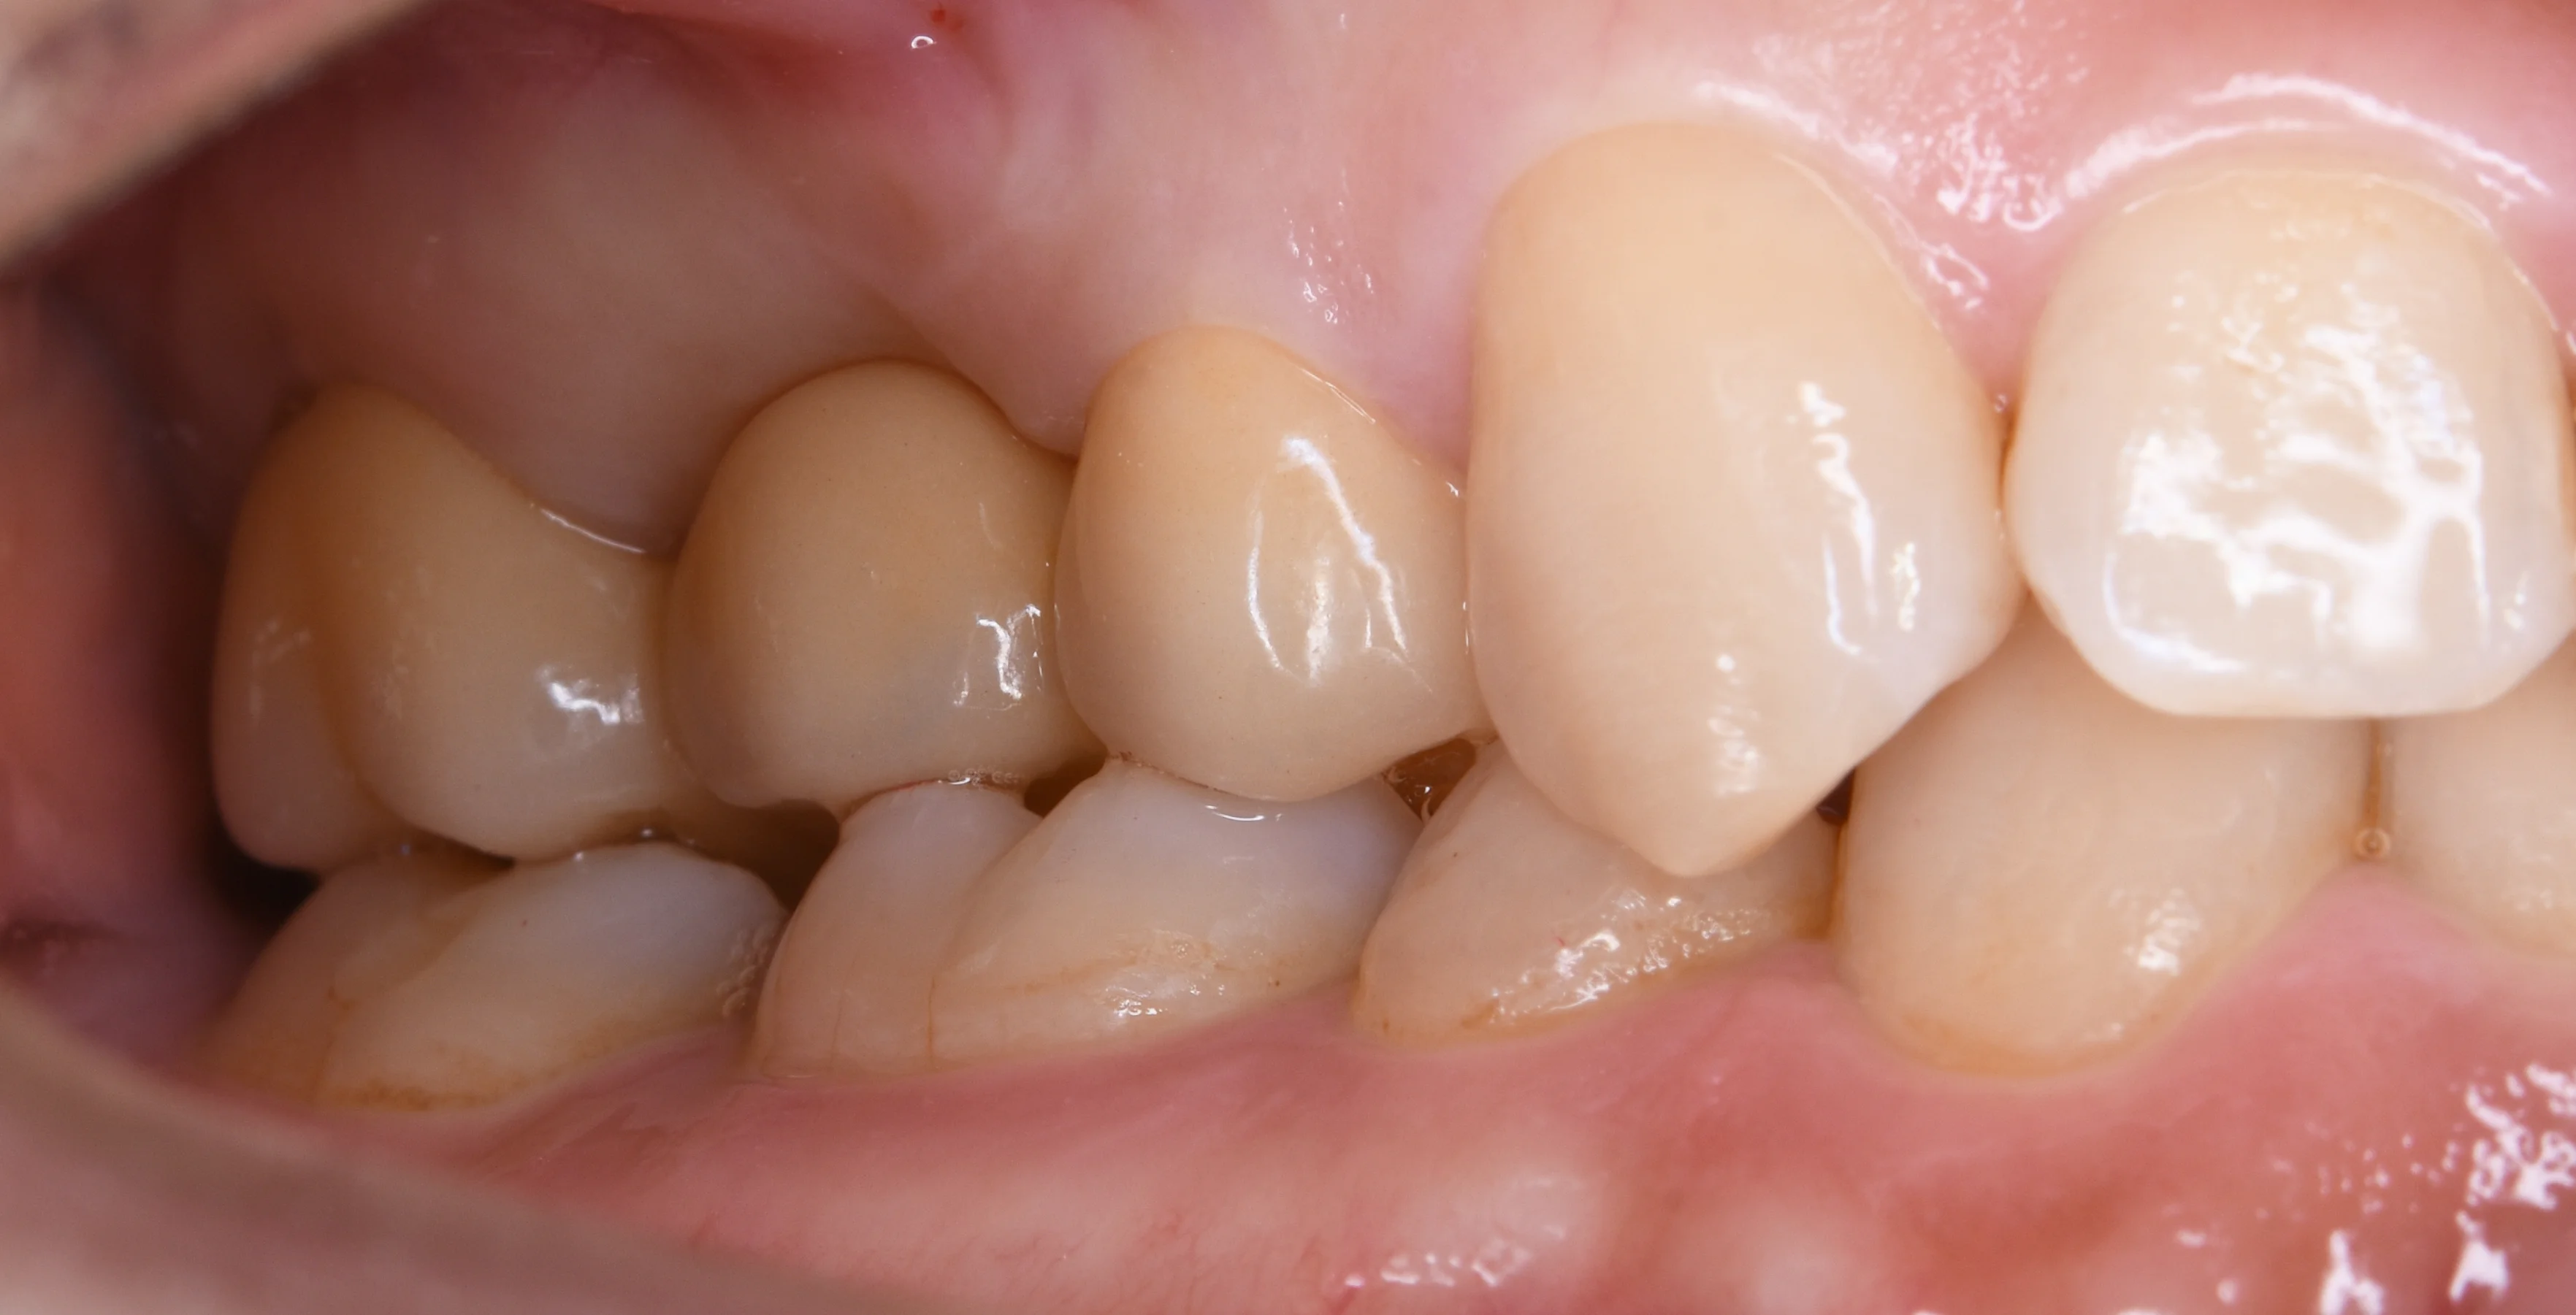

土台の状態の写真からです。

セラミックのブリッジ|坂寄歯科医院(取手市藤代)

仮歯も丁寧にやると歯茎の形態を綺麗に作っておくことが出来ます。

そうすると仕上がってくるセラミックが非常に綺麗に入るので、たかが仮歯といえどもしっかりと作るのが大事ですね。

歯の周りの歯茎がシャープになっているのがなんとなくわかるかと思います。